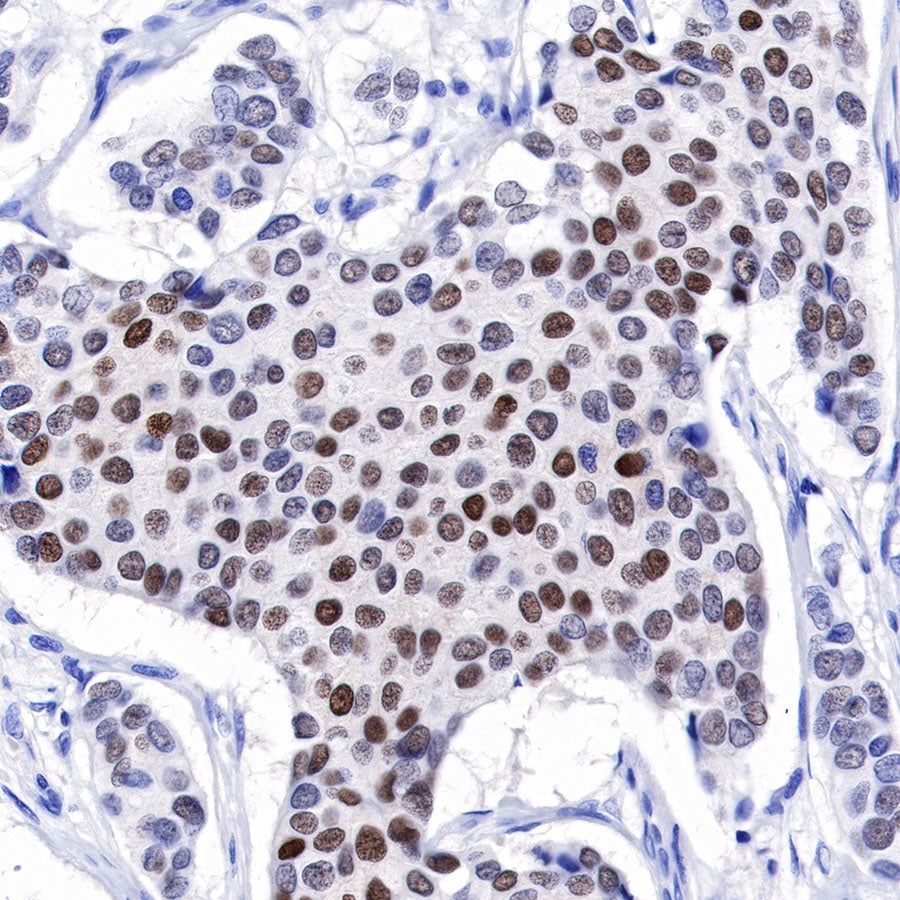

IHC shows positive staining in paraffin-embedded human breast cancer. Anti-Progesterone Receptor antibody was used at 1/500 dilution, followed by a HRP Polymer for Mouse & Rabbit IgG (ready to use). Counterstained with hematoxylin. Heat mediated antigen retrieval with Tris/EDTA buffer pH9.0 was performed before commencing with IHC staining protocol.